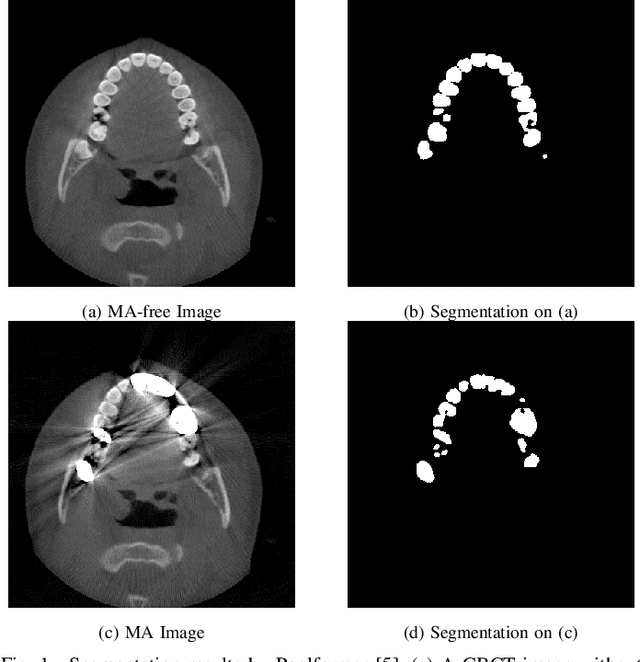

Abstract:Cone Beam Computed Tomography (CBCT) plays a key role in dental diagnosis and surgery. However, the metal teeth implants could bring annoying metal artifacts during the CBCT imaging process, interfering diagnosis and downstream processing such as tooth segmentation. In this paper, we develop an efficient Transformer to perform metal artifacts reduction (MAR) from dental CBCT images. The proposed MAR Transformer (MARformer) reduces computation complexity in the multihead self-attention by a new Dimension-Reduced Self-Attention (DRSA) module, based on that the CBCT images have globally similar structure. A Patch-wise Perceptive Feed Forward Network (P2FFN) is also proposed to perceive local image information for fine-grained restoration. Experimental results on CBCT images with synthetic and real-world metal artifacts show that our MARformer is efficient and outperforms previous MAR methods and two restoration Transformers.